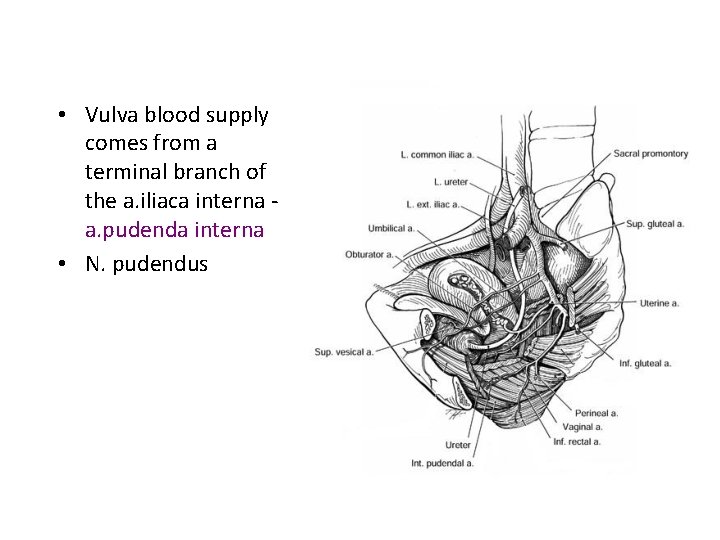

• Vulva blood supply comes from a terminal branch of the a. iliaca interna - a. pudenda interna • N. pudendus